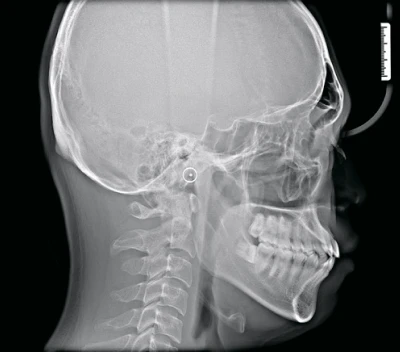

Самая современная технология для обеспечения качества изображения высокой чёткости

Сканирование при помощи цефалостата с прямым преобразованием или при помощи одноразовых датчиков цефалометрии. Одноразовый датчик цефалометрии захватывает изображения всего за 0,8 секунды, сводя к минимуму искажения и уменьшая облучение пациента. В то время как прямое преобразование обеспечивает сканирование с высоким разрешением.

Сканирование с прямым преобразованием

Цефалостат One-shot большой